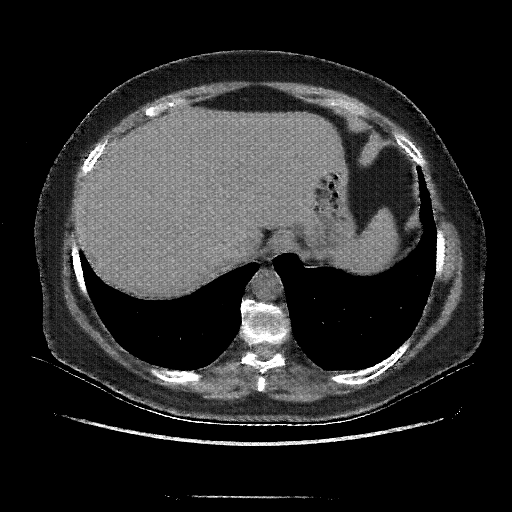

Generated VENOUS CT scan (A→B translation)

No window - Raw intensity values

Lung window (WL -600, WW 1500 β†’ Low βˆ’1350, High +150)

Mediastinum window (WL 40, WW 400 β†’ Low βˆ’160, High +240)